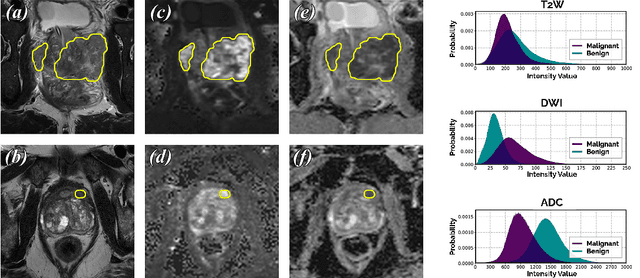

Abstract:We hypothesize that probabilistic voxel-level classification of anatomy and malignancy in prostate MRI, although typically posed as near-identical segmentation tasks via U-Nets, require different loss functions for optimal performance due to inherent differences in their clinical objectives. We investigate distribution, region and boundary-based loss functions for both tasks across 200 patient exams from the publicly-available ProstateX dataset. For evaluation, we conduct a thorough comparative analysis of model predictions and calibration, measured with respect to multi-class volume segmentation of the prostate anatomy (whole-gland, transitional zone, peripheral zone), as well as, patient-level diagnosis and lesion-level detection of clinically significant prostate cancer. Notably, we find that distribution-based loss functions (in particular, focal loss) are well-suited for diagnostic or panoptic segmentation tasks such as lesion detection, primarily due to their implicit property of inducing better calibration. Meanwhile, (with the exception of focal loss) both distribution and region/boundary-based loss functions perform equally well for anatomical or semantic segmentation tasks, such as quantification of organ shape, size and boundaries.